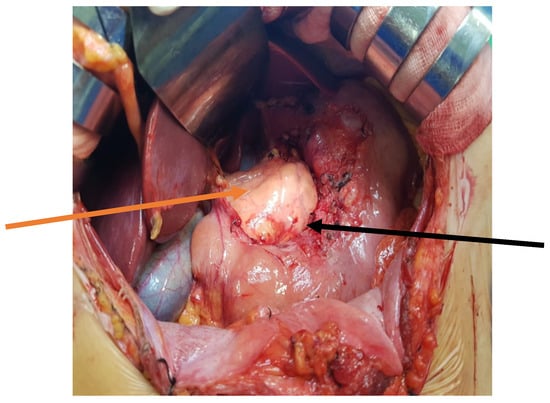

Three-phase computed tomography (CT) scan revealed an extensive mass measuring 10 × 4 cm between the left segments of the liver and the lesser curvature of the stomach. The lesion was well-defined, fluid dense, and did not contain solid elements. Within it, there were vessels with an undistorted course. The mass occupied the space in front of the body and tail of the pancreas, descending further down the back of the stomach and duodenum. (Figure 1A,B).

Figure 1. (A,B) Computed tomography (CT) image of the abdominal cavity. There is a visible mass located at the lesser curvature of the stomach (orange arrows).